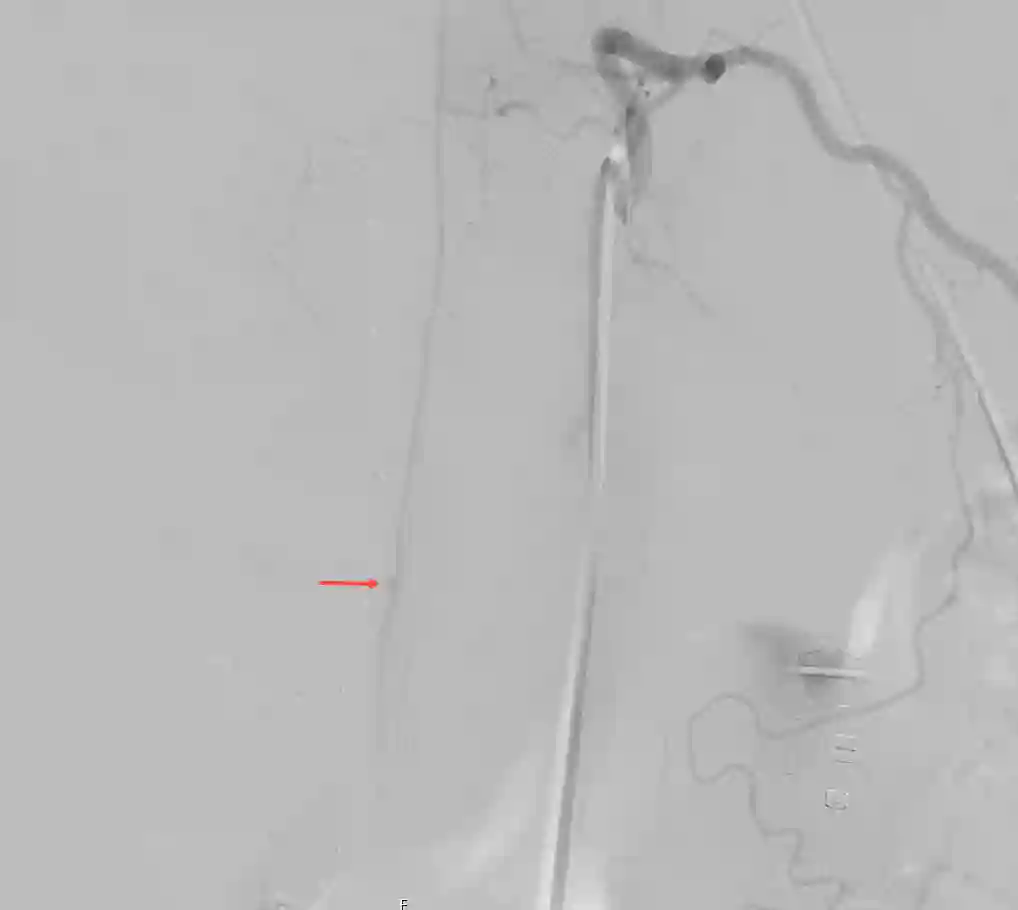

Arteria spinalis anterior Aneurysma Angiographie

Spinale DSA eines Patienten mit einem Aneurysma der Arteria spinalis anterior.